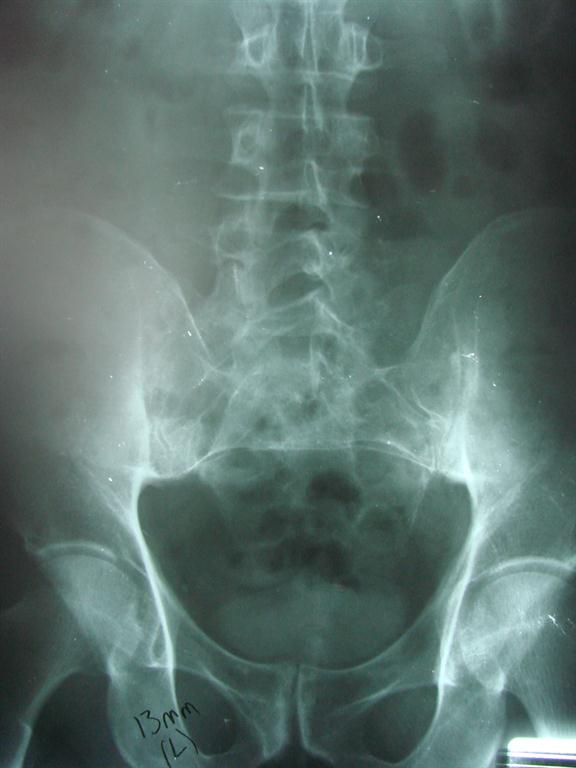

A short leg can be due to a variety of situations that the doctor may address first before addressing your short leg. We at Aurora Chiropractic Center will determine if the short leg is truly due to structure. If it is, you will likely be fitted with a heel lift to correct the inequality. If the inequality is larger, you may need to add a little at a time to allow your spine to adjust. In addition to correcting the difference, your chiropractic physician will align your spine with spinal manipulation.

A thorough, clinical examination that may include imaging is important to your short leg diagnosis and management.